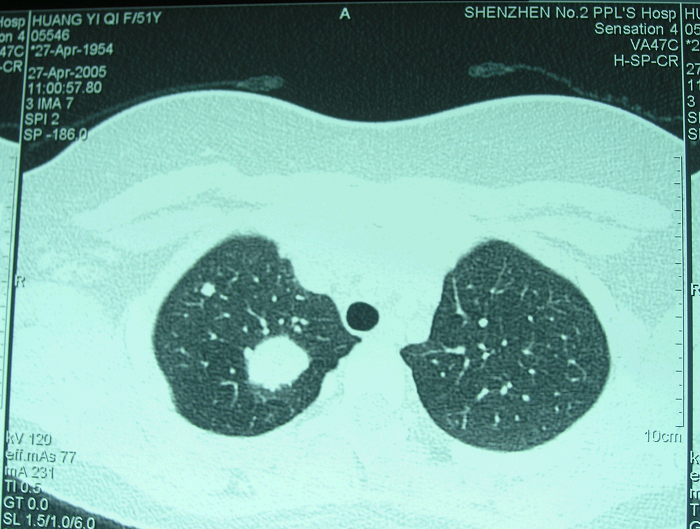

2、病例2:女 10岁 左股骨下端普通型骨肉瘤并病理性骨折,大剂量化疗后行肿瘤边缘切除定制型假体置换术,术后局部复发截肢,2年后肺转移死亡。

图 12 术后1年肺转移